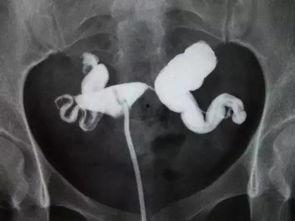

想象输卵管就像一条管道,连接着卵巢和子宫。正常情况下,卵巢每个月会排出一个卵子,卵子通过输卵管进入子宫。但如果输卵管内部积水,这条管道就会被堵塞,卵子就无法顺利通过,这就会影响到女性的生育能力。

3. 手术过程:医生会通过腹腔镜,也就是一种细长的管子,进入你的腹部。这个管子上有摄像头,可以实时传输手术画面。医生会仔细观察你的输卵管,找到积水的地方,然后进行手术。

1. 手术开始:医生首先将腹腔镜插入你的腹部,然后通过摄像头观察输卵管的情况。

2. 找到积水部位:医生会仔细寻找积水的地方,并用工具将其清除。